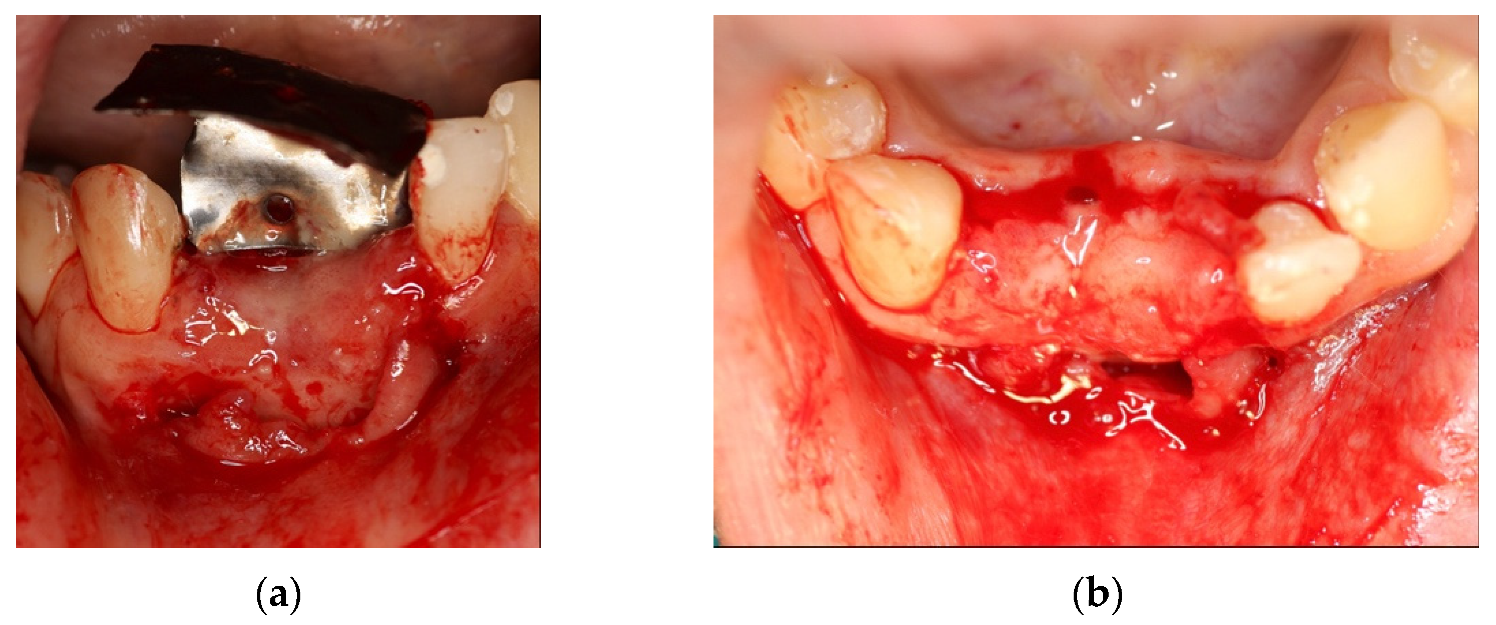

4.2. Clinical Case n.2.

4.3. Clinical Case n.3.

4.4. Clinical Case n.4.